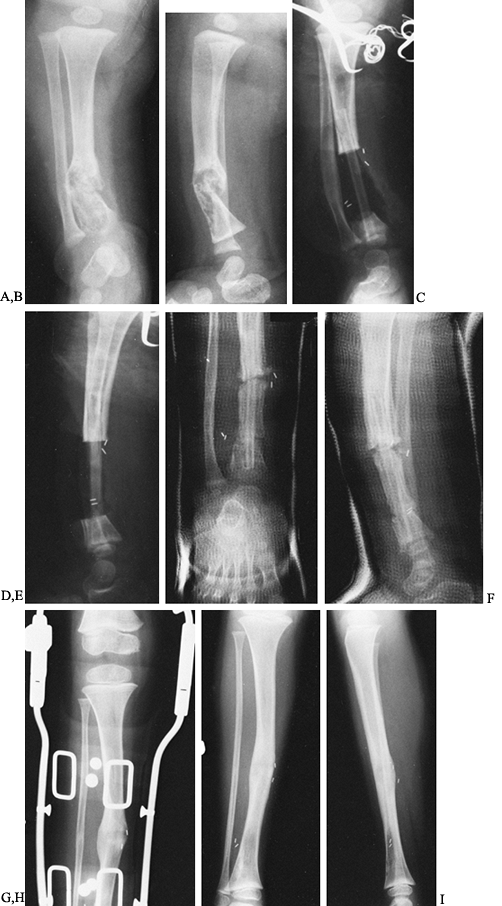

deformities secondary to achondroplasia must be surgical because

procedure is a proximal tibial valgus osteotomy and proximal fibular

epiphysiodesis (Fig. 169.11). The latter must

![]() |

Figure 169.11. A:

Standing preoperative radiographs of a 6-year-old Caucasian boy with achondroplasia genu varum demonstrating the typical epiphyseal and metaphyseal changes, as well as overgrowth of the fibulae. B: Postoperative radiograph after proximal tibial and fibular diaphyseal valgus derotation osteotomies of the right leg shows that internal fixation was achieved with percutaneous smooth Steinmann pins. C: Postoperative radiograph of the left lower leg. D: Standing radiographs 6 months postoperatively demonstrates satisfactory healing and excellent correction of the genu varum deformities. |